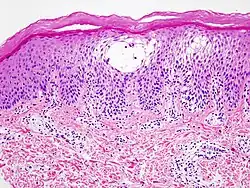

Le microbiote cutané humain (ou « microflore » de la peau humaine) est la communauté de microorganismes opportunistes, saprobiontes, souvent symbiotes[1] et parfois pathogènes qui composent la « flore cutanée ». C'est la partie externe du microbiote de l'organisme humain. De manière générale, la biodiversité bactérienne limite le risque de colonisation de la peau par une bactérie pathogène et constitue une protection contre l'inflammation de la peau[2]. Une partie du microbiote cutané est partagé avec le microbiote des muqueuses, notamment respiratoires[3].

En raison de la taille microscopique des organismes qui la composent, la microflore humaine est invisible à nos yeux. La peau d'un adulte héberge en moyenne 1012 (mille milliards) bactéries (soit 50 millions par cm2 de peau)[4],[5] de plus de 500 espèces différentes[6]. La peau supporte et entretient naturellement son propre « micro-écosystème ». Celui-ci se forme à la naissance, puis évolue jusqu'à la mort. Cet « écosystème » est étudié depuis quelques décennies en tant que tel.

Une peau saine est recouverte de biofilms adaptés aux différentes parties du corps. Ces biofilms naturels sont plus stables, résistants et protecteurs contre d'autres bactéries quand ils abritent une diversité d'espèces et de groupes de micro-organismes[54].

Inversement, la peau malade est généralement uniformément colonisée par une ou quelques espèces qui ont accidentellement trouvé des conditions leur permettant de proliférer anormalement et parfois d'empêcher toute cicatrisation[55]. Par exemple, un biofilm monospécifique de Staphylococcus aureus (qui peut atteindre son extension maximale en 3 jours) cause une dermatite atopique sèche difficile à soigner[56] et un biofilm monospécifique de Propionibacterium acnes est source d'acné[56],[57].